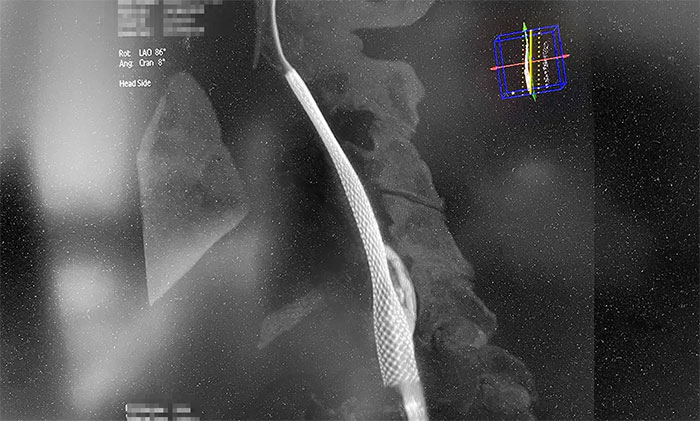

術(shù)中,超滑導(dǎo)絲、多功能導(dǎo)管經(jīng)過反復(fù)嘗試順利通過左頸內(nèi)動(dòng)脈起始段,到達(dá)左頸內(nèi)動(dòng)脈遠(yuǎn)端顯影段,路圖見遠(yuǎn)端血管通暢,左大腦中動(dòng)脈顯影;隨后,微導(dǎo)絲經(jīng)多功能導(dǎo)管置于左頸內(nèi)動(dòng)脈海綿竇段,經(jīng)微導(dǎo)絲送入保護(hù)傘至左頸內(nèi)動(dòng)脈巖骨垂直段并釋放,再沿保護(hù)傘微導(dǎo)絲送入4x30mm球囊于左頸內(nèi)動(dòng)脈起始段,給予球囊擴(kuò)張,撤除球囊后造影見左頸內(nèi)動(dòng)脈起始段再通,左頸內(nèi)動(dòng)脈、左大腦中動(dòng)脈顯影;最后,送入9x50mm支架,釋放于左頸內(nèi)動(dòng)脈頸段至左頸總動(dòng)脈末段,造影見左頸內(nèi)動(dòng)脈起始段顯影明顯改善,左頸內(nèi)動(dòng)脈、左大腦中動(dòng)脈、左大腦前動(dòng)脈顯影可,行3D造影見左頸內(nèi)動(dòng)脈頸段顯影改善。行支架CT見支架成形可,行XperCT未見顱內(nèi)出血。

▲ 左側(cè)頸內(nèi)動(dòng)脈閉塞順利開通